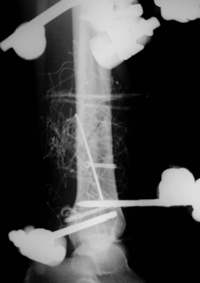

Distale Tibiafraktur mit Weichteilschaden

Die Stabilisierung erfolgte minimal invasiv.

2Tage nach der Operation. Schrauben und Drähte wurden weichteilschonend mit Stichincisionen eingebracht.